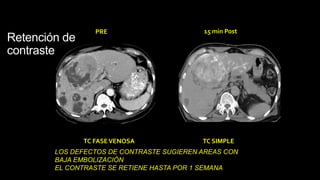

Retención de

contraste

PRE 15 min Post

TC FASEVENOSA TC SIMPLE

LOS DEFECTOS DE CONTRASTE SUGIEREN AREAS CON

BAJA EMBOLIZACIÓN

EL CONTRASTE SE RETIENE HASTA POR 1 SEMANA